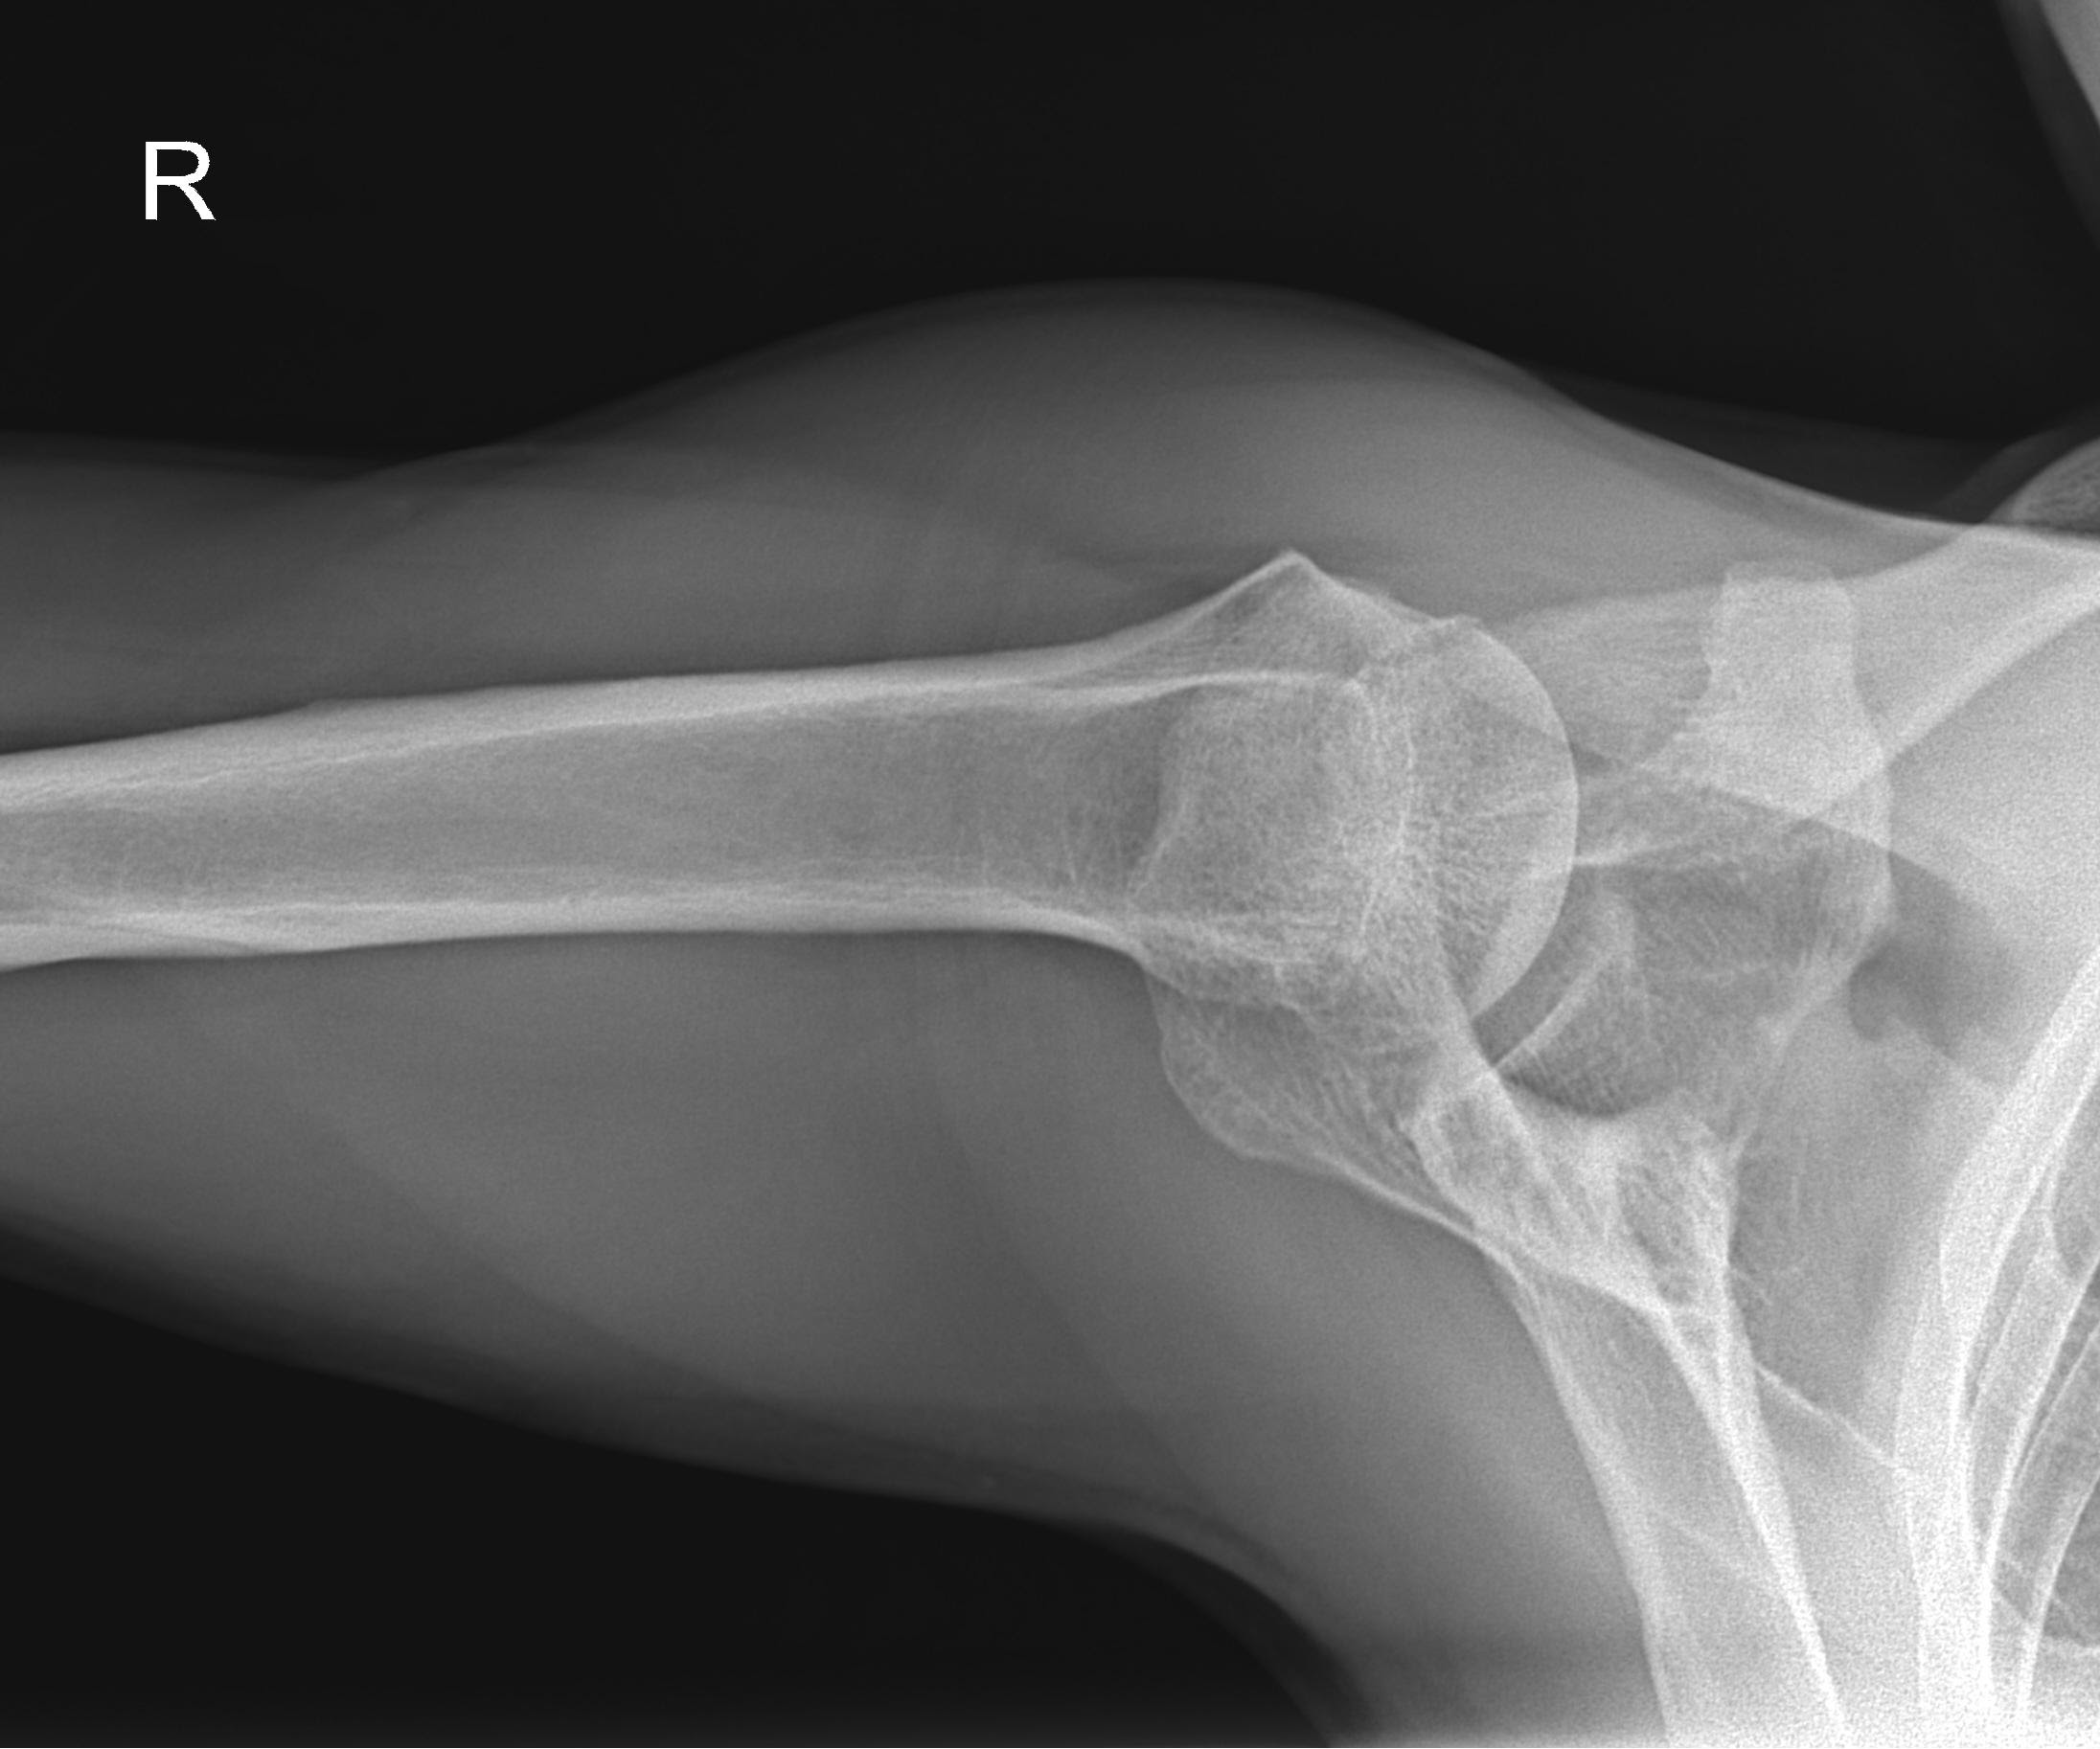

The Axillary View is a specialized X-ray projection primarily used to evaluate the shoulder joint, specifically the relationship between the humeral head and the glenoid cavity of the scapula. In this view, the X-ray beam is directed through the axilla (armpit), with the patient either in a supine position with the arm abducted 90°, or in a seated or standing position using variations like the modified Bernageau or West Point view. The axillary view is particularly useful for detecting anterior or posterior shoulder dislocations, glenoid fractures, and joint space abnormalities, offering a clear image of the glenohumeral articulation from a perpendicular angle.

Axillary view